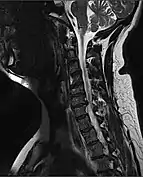

Diagnosis

A person's presentation in context of trauma or non-traumatic background determines suspicion for a spinal cord injury. The features are namely paralysis, sensory loss, or both at any level. Other symptoms may include incontinence.[89]

A radiographic evaluation using an X-ray, CT scan, or MRI can determine if there is damage to the spinal column and where it is located.[9] X-rays are commonly available[88] and can detect instability or misalignment of the spinal column, but do not give very detailed images and can miss injuries to the spinal cord or displacement of ligaments or disks that do not have accompanying spinal column damage.[9] Thus when X-ray findings are normal but SCI is still suspected due to pain or SCI symptoms, CT or MRI scans are used.[88] CT gives greater detail than X-rays, but exposes the patient to more radiation,[90] and it still does not give images of the spinal cord or ligaments; MRI shows body structures in the greatest detail.[9] Thus it is the standard for anyone who has neurological deficits found in SCI or is thought to have an unstable spinal column injury.[91]